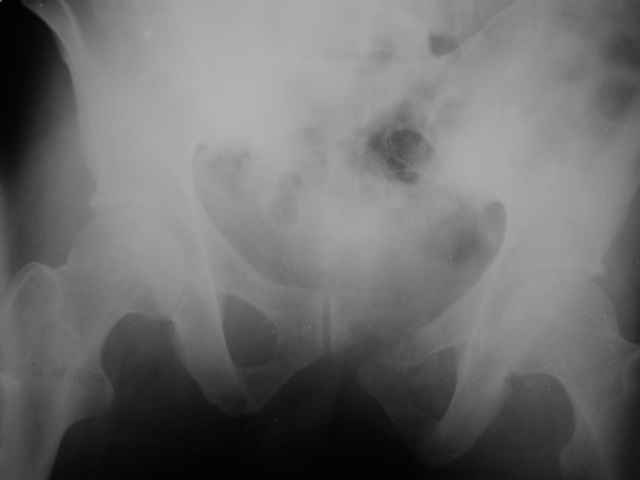

Выполнили операцию "желтому мужчине"(суррогаты так и продолжают пить)! С диагнозом:Перелом костей таза с нарушением тазового кольца

(перелом лонной ,седалищной костей справа .Разрыв КПС слева)Открытый (1 А Каплан) оскольчатый перелом проксимального эпиметафиза большеберцовой кости.

Сделали на 14 сутки остеосинтез б/берцовой кости мыщелковой пластиной LCP, остеосинтез костей таза АВФ(передняя опора, извинямси за качество R-грамм). Сохраняется смещение. Попытаемся его устранить этапно, но сомневаемся хватит ли жесткости АВФ и нет нигде меодики введения илиосакральных винтов!